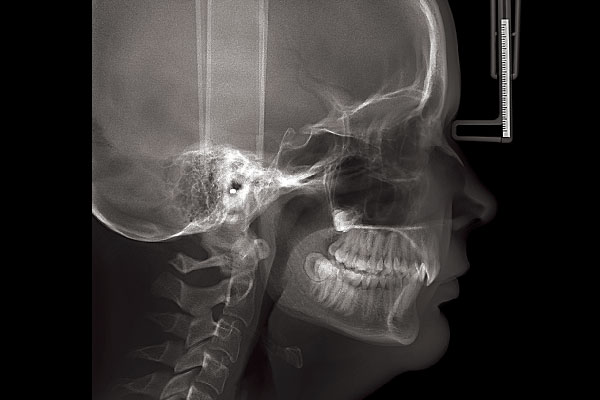

セファロ付き歯科用CT